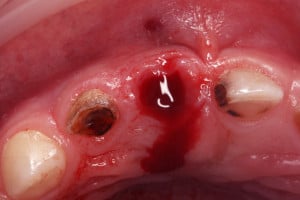

Plan leczenia zakładał usunięcie mesiodens’a z dojściem od strony szczytu wyrostka. W znieczuleniu nasiękowym CYTOKARTIN (1/3 ampułki) przeprowadzoną prostą ekstrakcję zębową zaopatrzono gąbką kolagenową.